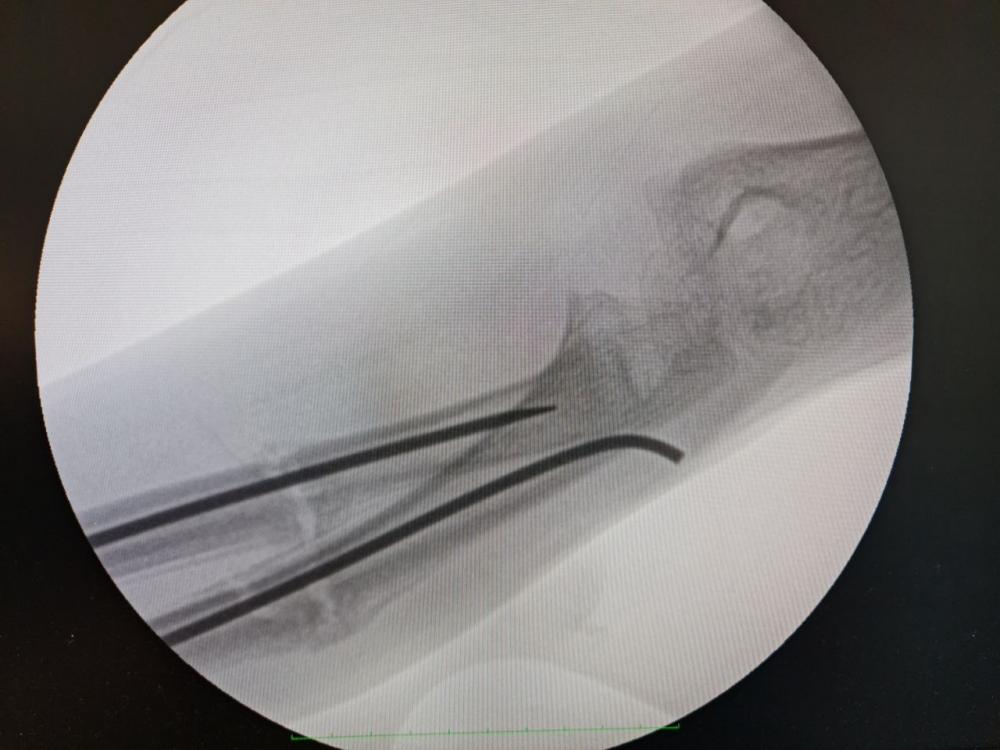

Саме тому і вирішили провести дитині так звану «остеоклазію кісток передпліччя із внутрішньою фіксацією титановими еластичними стрижнями».

«Остеоклазія- це операція штучного перелому в місці зрощення під рентген-контролем з метою співставити уламки кісток та зафіксувати їх за допомогою титанових еластичних стрижнів", - розповідають медики.